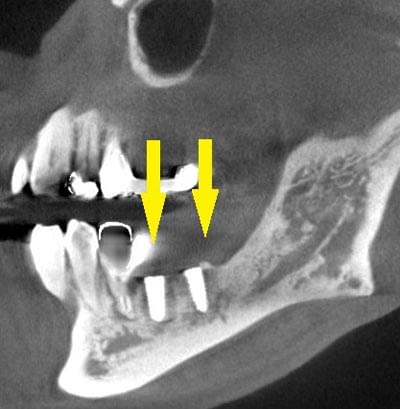

患者様のインプラント治療前のレントゲン写真です。右下顎大臼歯2本の抜歯後のレントゲン写真で、写真の黄色矢印は、歯の周囲の歯槽骨が大きく吸収されてしまっていました。

写真のように、CTで見ると、骨吸収の様子が良く分かり、下顎骨の中を通る神経近くまで骨がありませんでした。